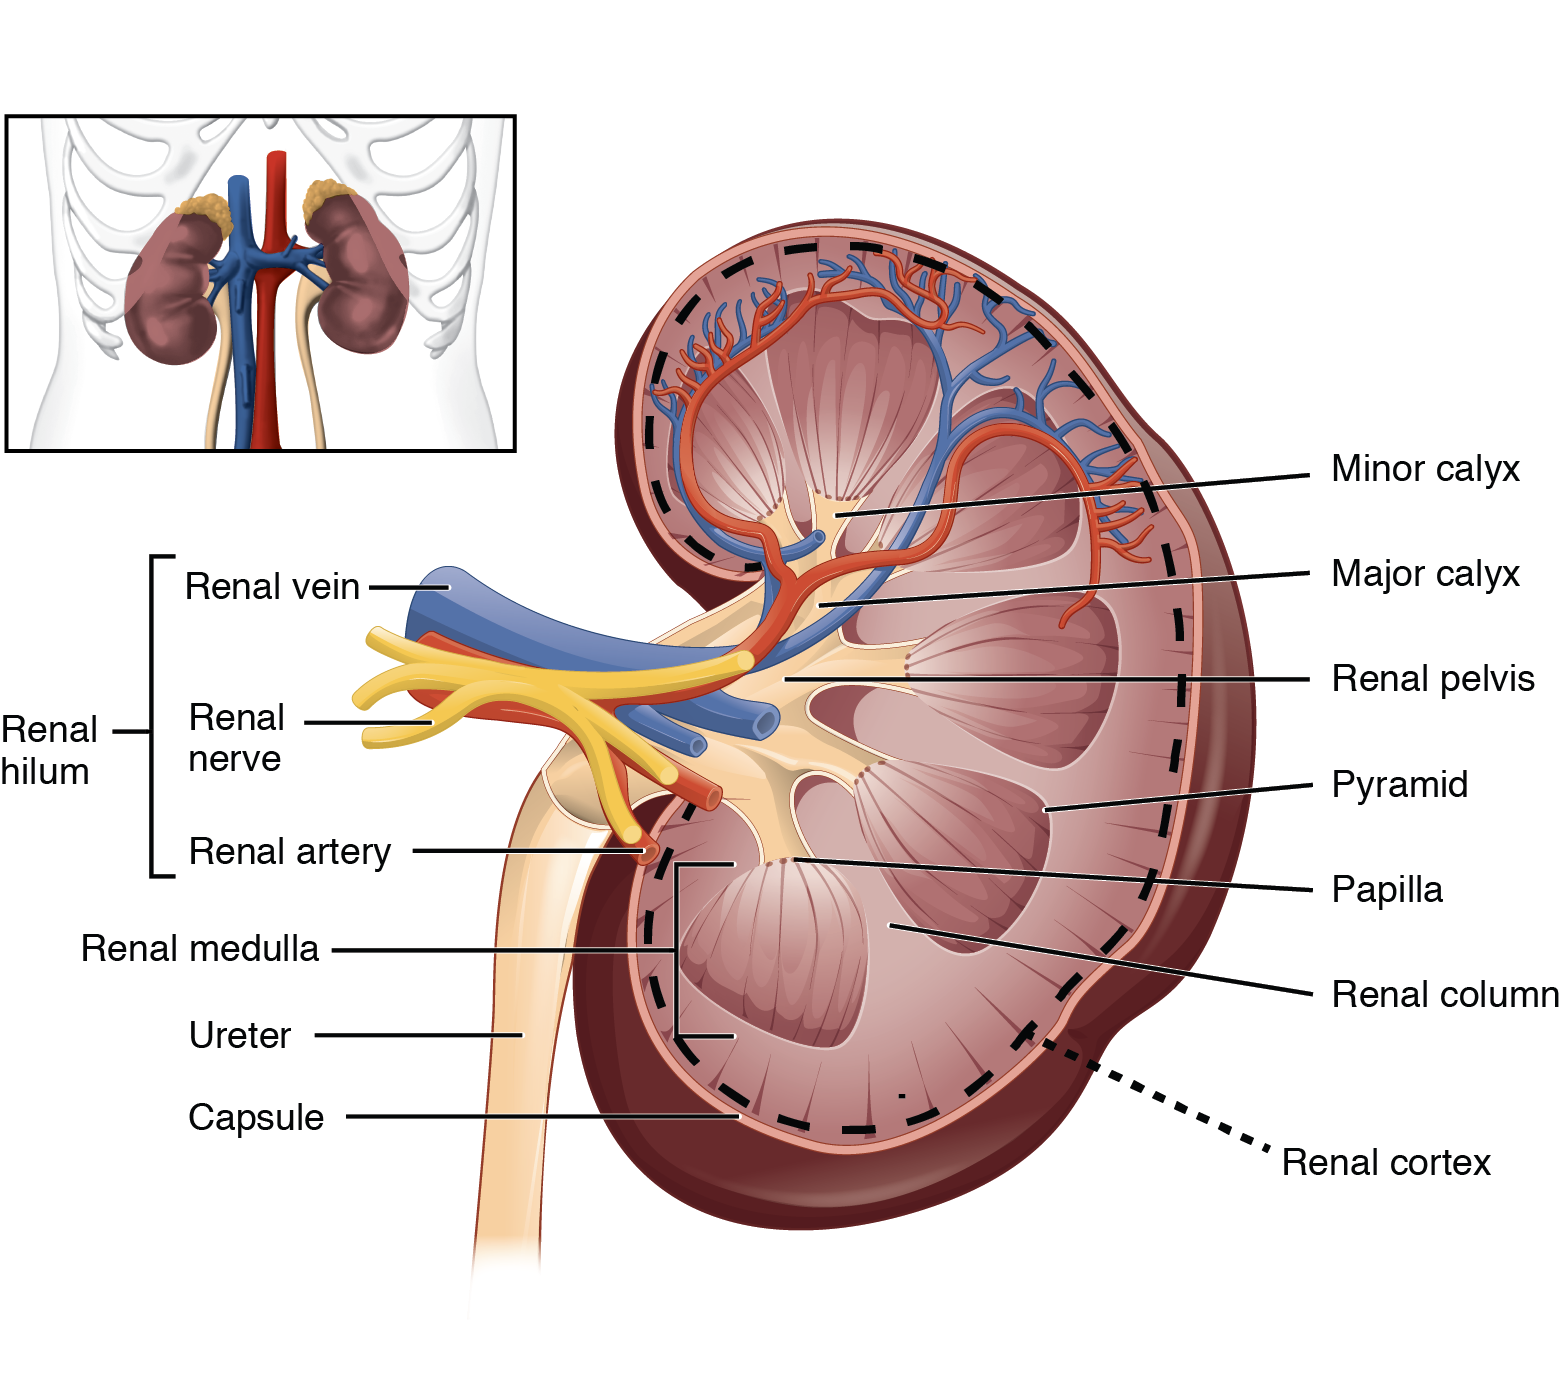

Строение почек человека: Фото и описание